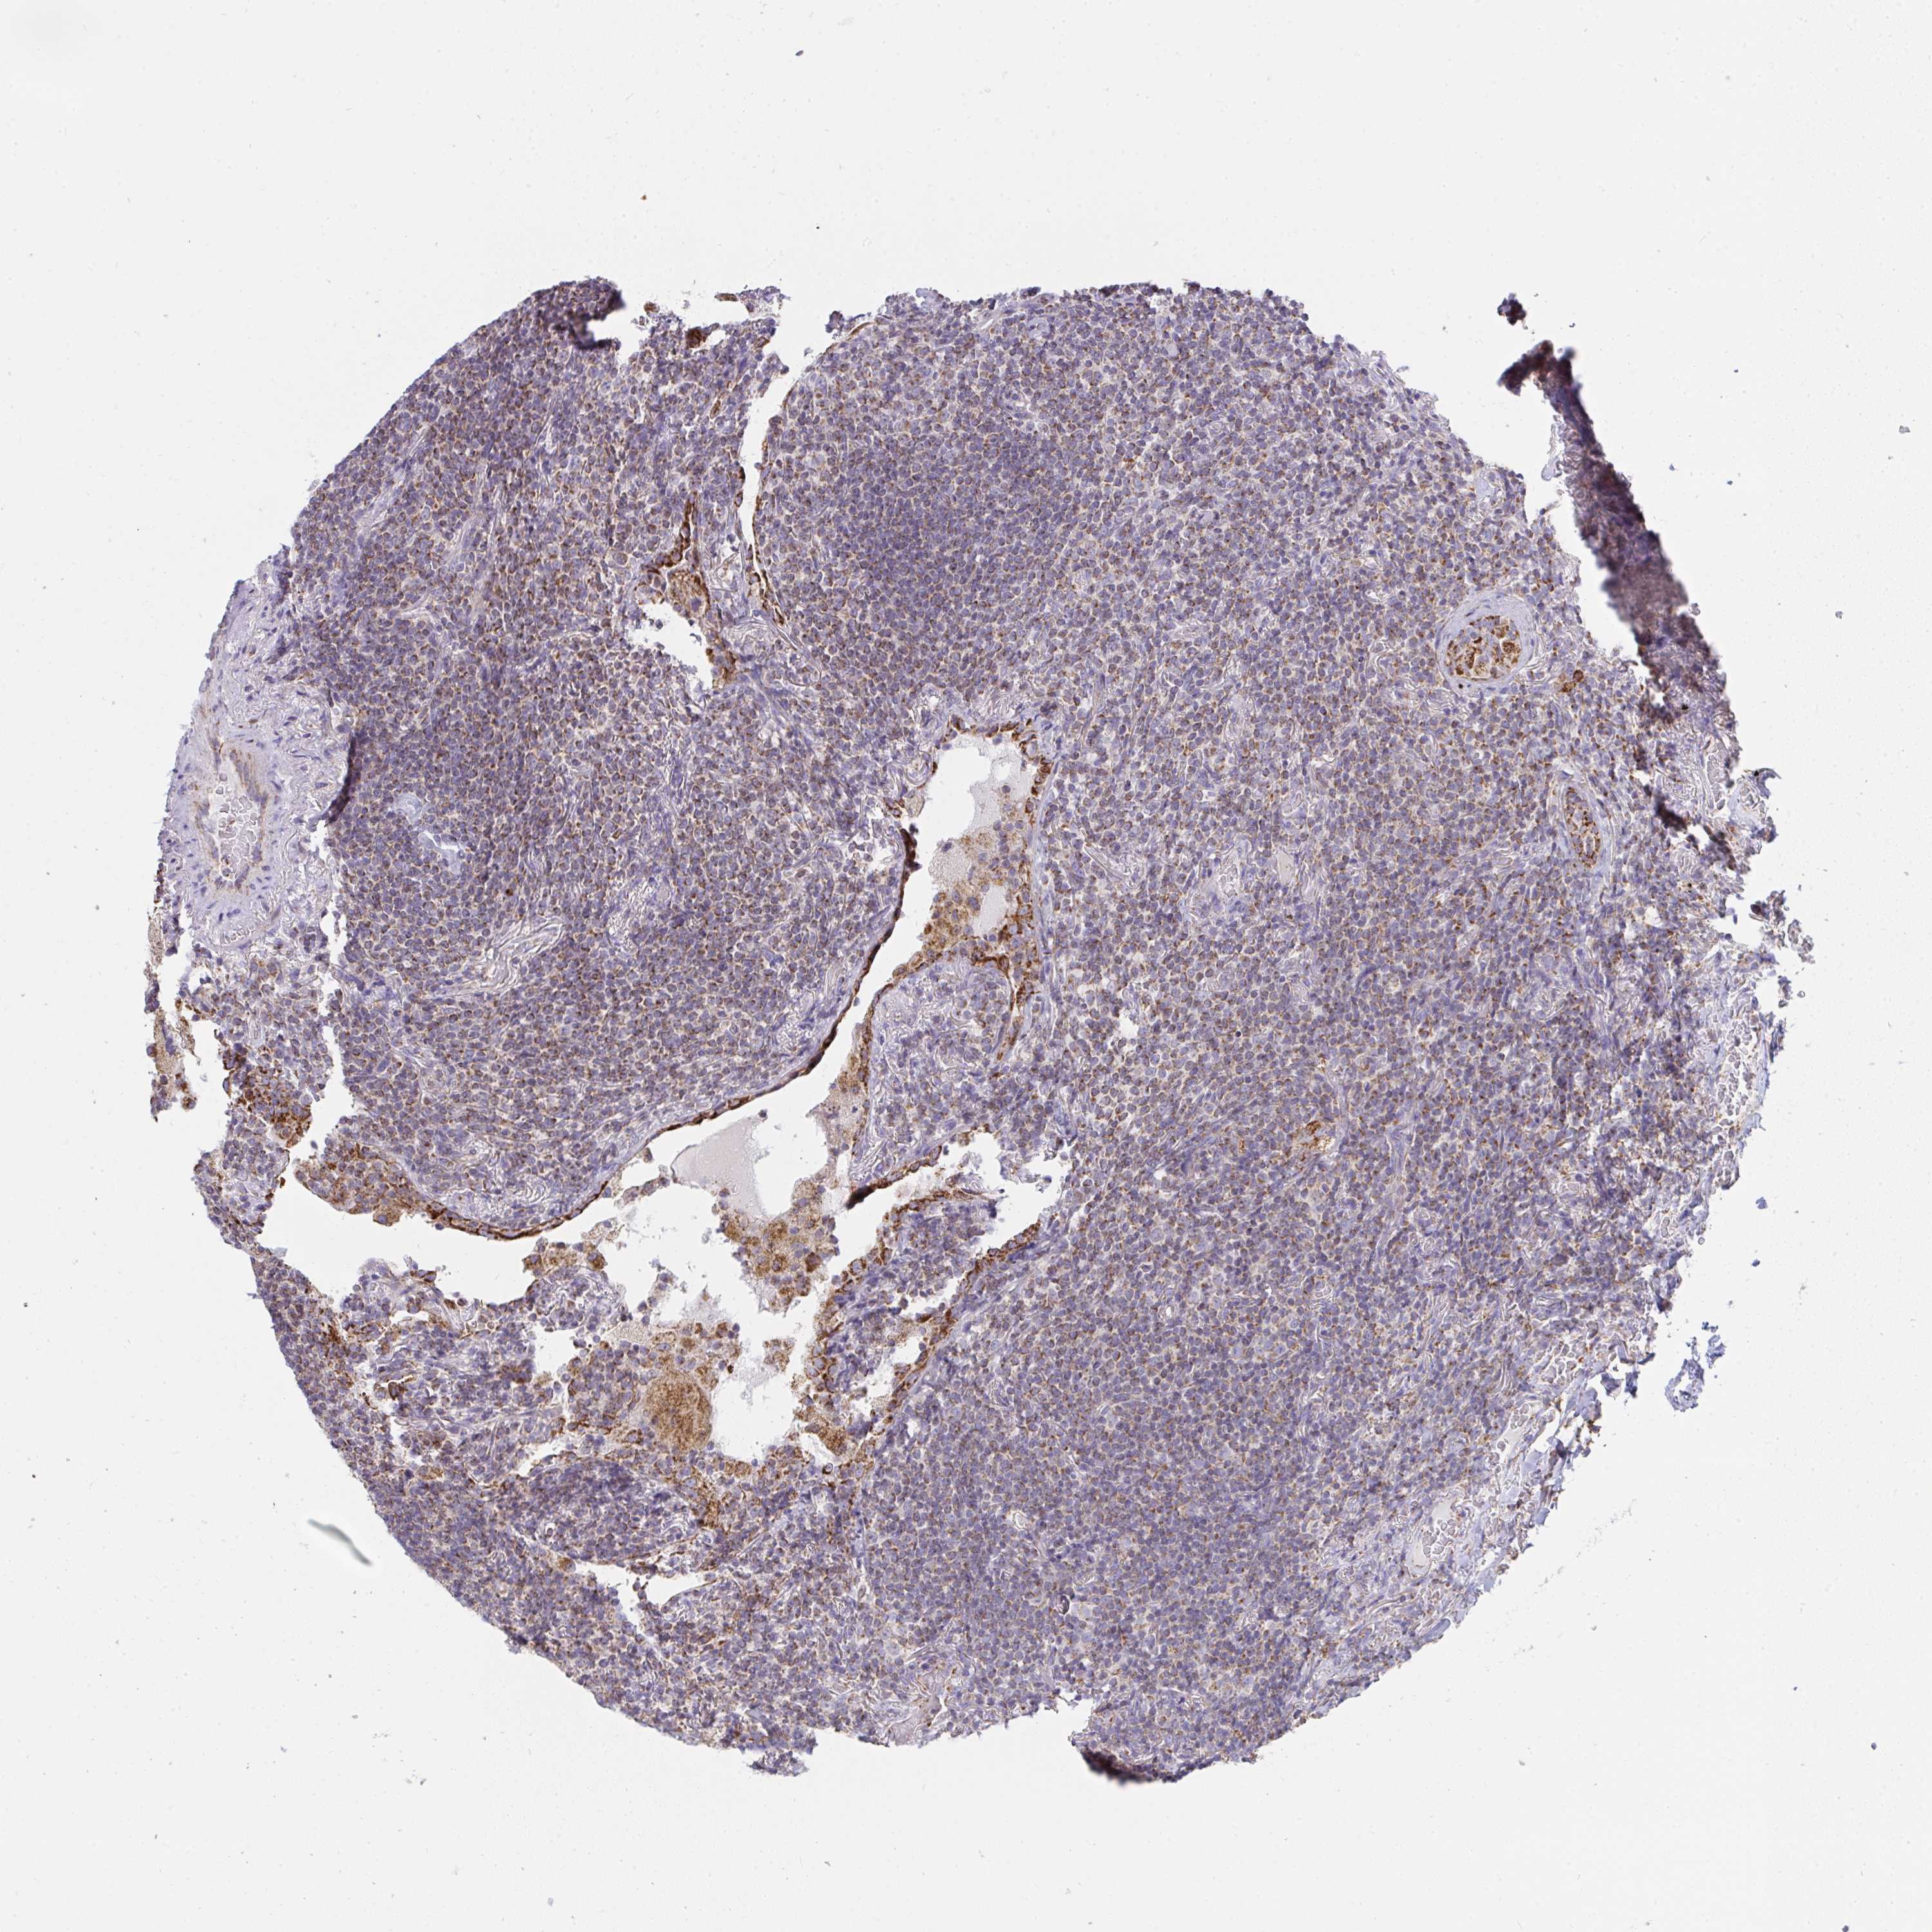

CANCER LYMPHOMA Show tissue menu

LYMPHOMA - Protein expressioni

A mouse-over function shows sample information and annotation data. Click on an image to view it in a full screen mode. Samples can be filtered based on level of antibody staining by selecting one or several of the following categories: high, medium, low and not detected. The assay and annotation is described here.

Each image is clickable and will lead to virtual microscopy that enables deeper exploration of all samples and also displays staining intensity scores, fraction scores and subcellular localization as well as patient and tissue information for each sample.

Antibody HPA043226

Antibody HPA043534

Antibody CAB025530

Malignant lymphoma, non-Hodgkin's type, Low grade

Malignant lymphoma, non-Hodgkin's type, High grade

Hodgkin's disease, NOS